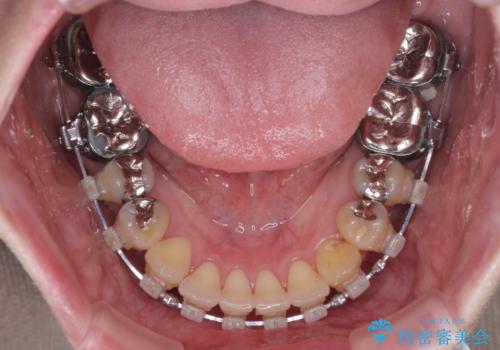

- 矯正装置

- クリアブラケット

- 治療期間

- 2年2ヶ月

前歯を早々に仮歯に置き換えたことで、矯正治療に意欲的に臨んでくださいました。